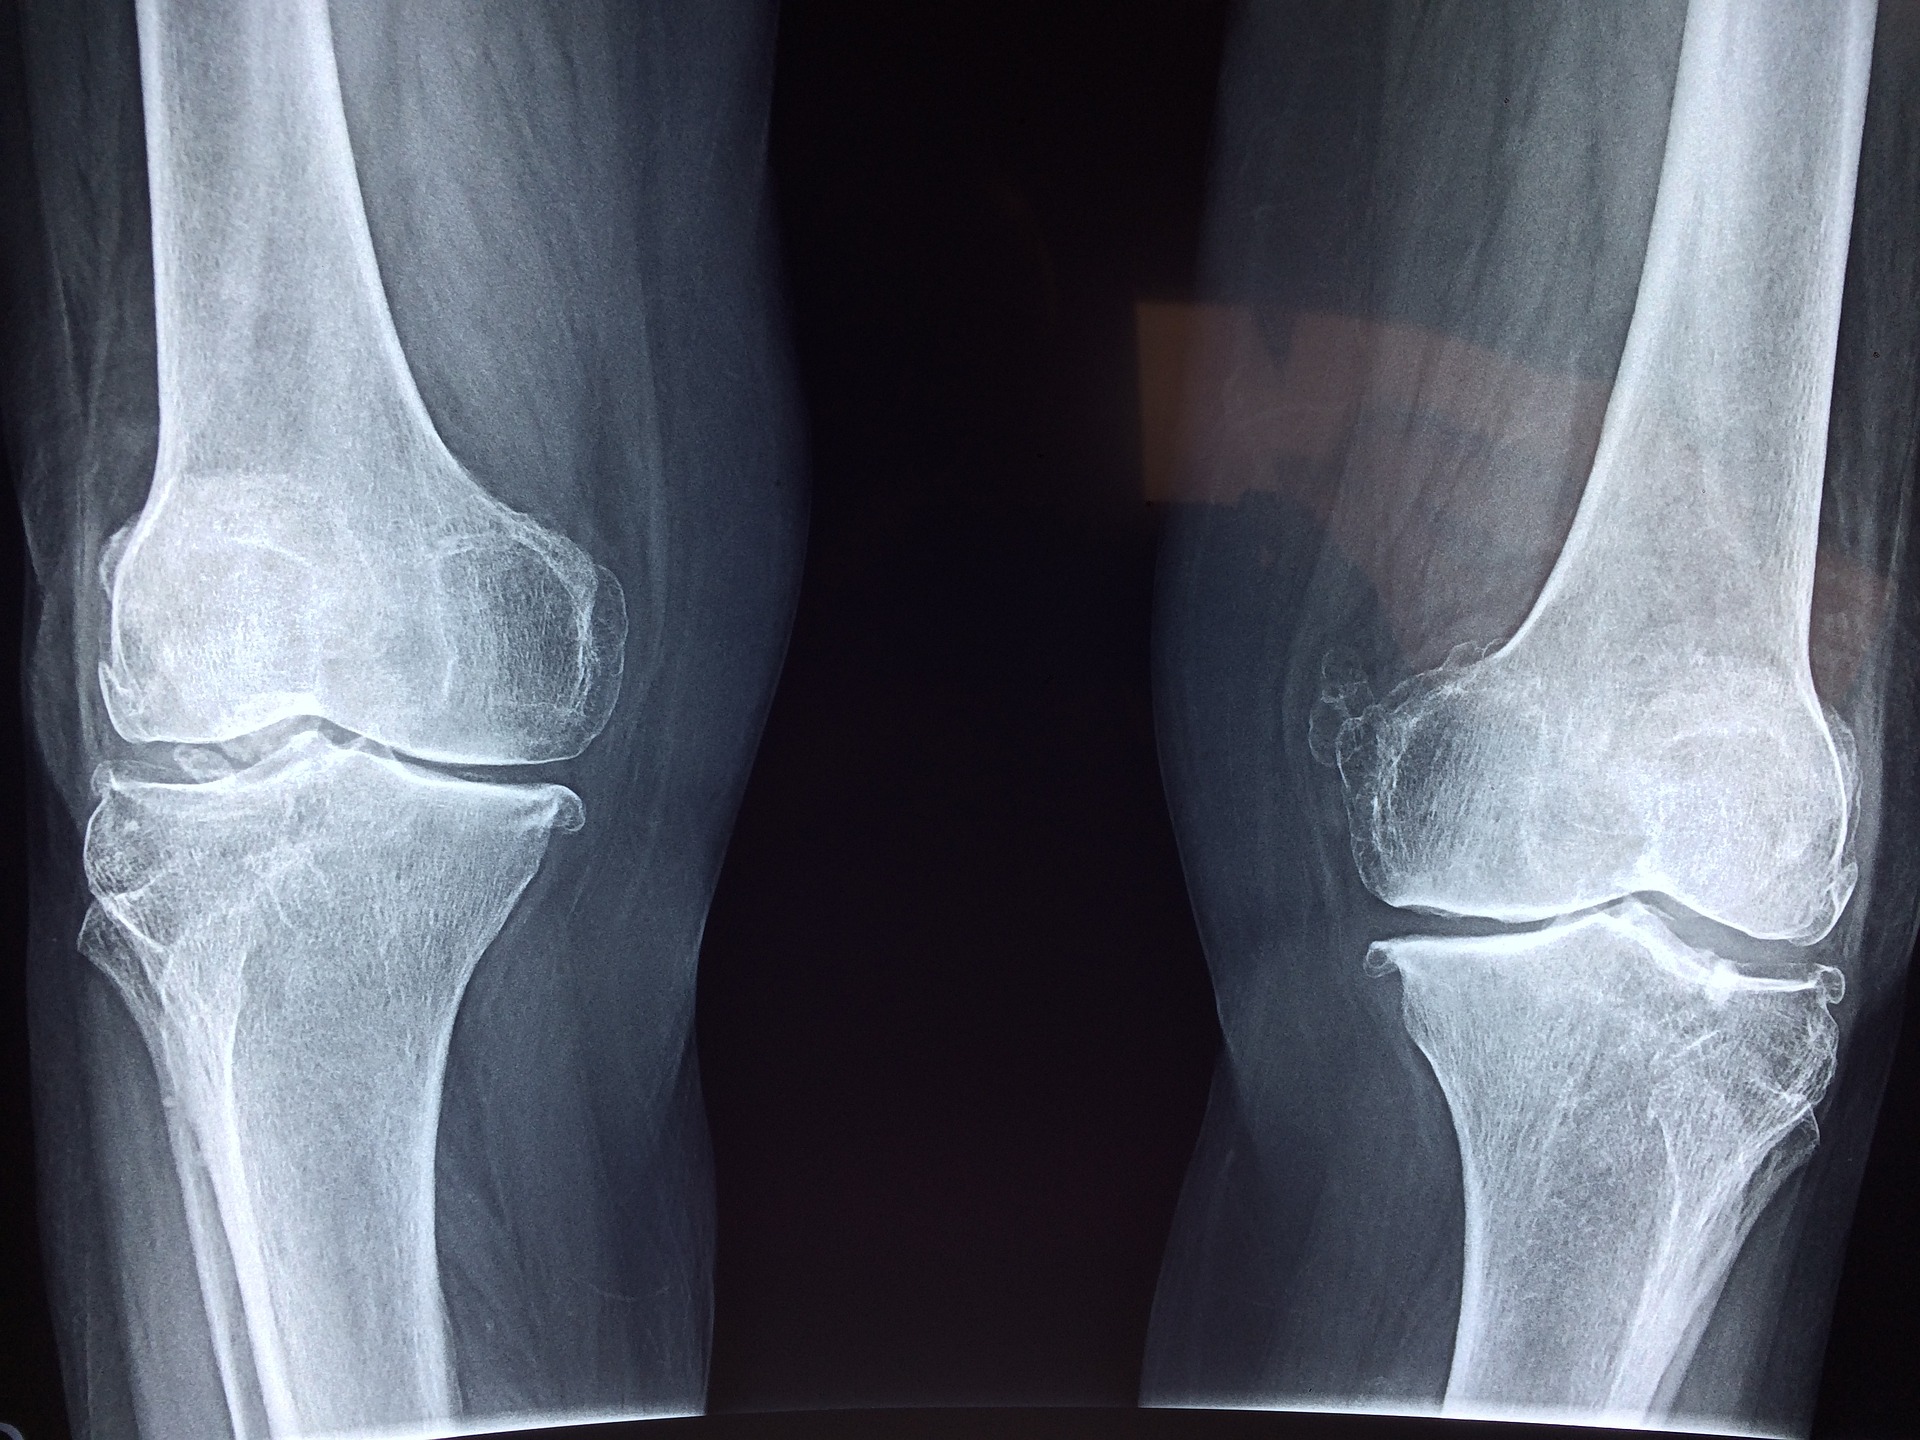

오늘은 뼈 밀도가 감소하여 뼈가 쉽게 파괴되는 질환인 골다공증에 대해서 알아보도록 하겠습니다. 주로 여성들이 많이 이 질환을 겪게 되는데, 골다공증은 뼈가 마르는 상태로 위험한 골절을 유발할 수 있기 때문에 조기 예방이 중요합니다. 그중에서도 영양제를 이용한 예방법이 유효한 방법의 하나입니다. 이번에는 골다공증 예방을 위한 영양제 섭취 방법과 골다공증에 대한 정보를 제공해 드리겠습니다.

고갈된 뼈조직을 재생하기 어려워지는 질환으로, 뼈의 밀도가 감소하여 뼈가 쉽게 파괴되는 증상이 일어납니다. 골다공증은 주로 50세 이상의 여성에서 발생하는데, 여성호르몬 수치의 감소가 원인 중 하나입니다. 일반적으로 골다공증의 초기 증상은 증상이 없으며, 골밀도 감소로 인한 골절 위험이 크게 높아집니다.

골밀도 검사 : 골밀도 검사는 골다공증 진단과 예방에 중요한 검사입니다. 골밀도 검사를 통해 뼈의 밀도를 측정하여 골다공증 위험을 파악할 수 있습니다.